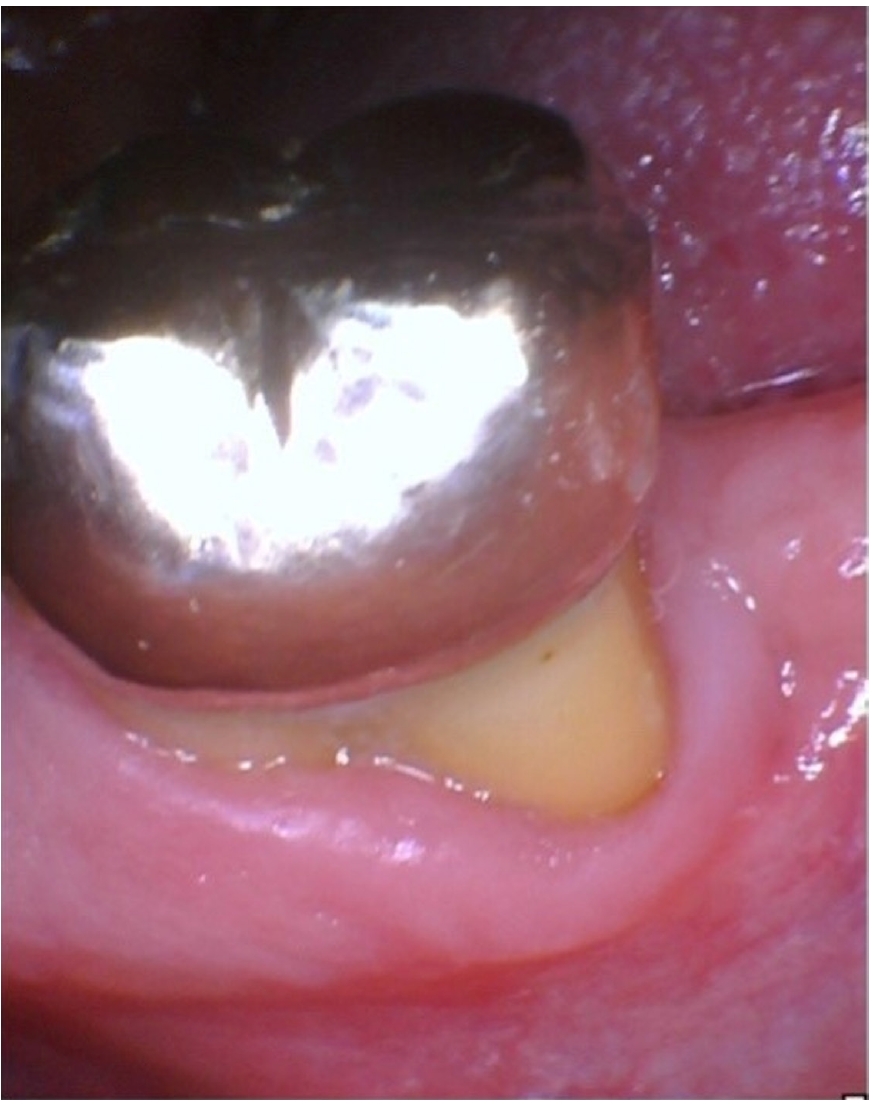

The patient was lost to follow-up until he reported again at 24 months, at which time clinical examination revealed that a full-coverage restoration on tooth #18 had been placed, restoring form and function (Figure 6). Clinical gingival health was noted on a reduced periodontium. Draining sinus tract remained resolved, and probing depths were improved to 3–4 mm. The tooth exhibited no mobility. Periapical radiograph (Figure 7) showed significant resolution of the periapical radiolucency with substantial bone regeneration along the length of the distal root. The patient was greatly appreciative that his natural dentition was conserved, which motivated him to ensure continued dental care maintenance.

Figure 6.

Twenty-four-month recall showing that the tooth has been restored with an extracoronal restoration and absence of draining sinus tract. Gingival health on a reduced periodontium is noted.

rde-2025-50-e31f6.jpg